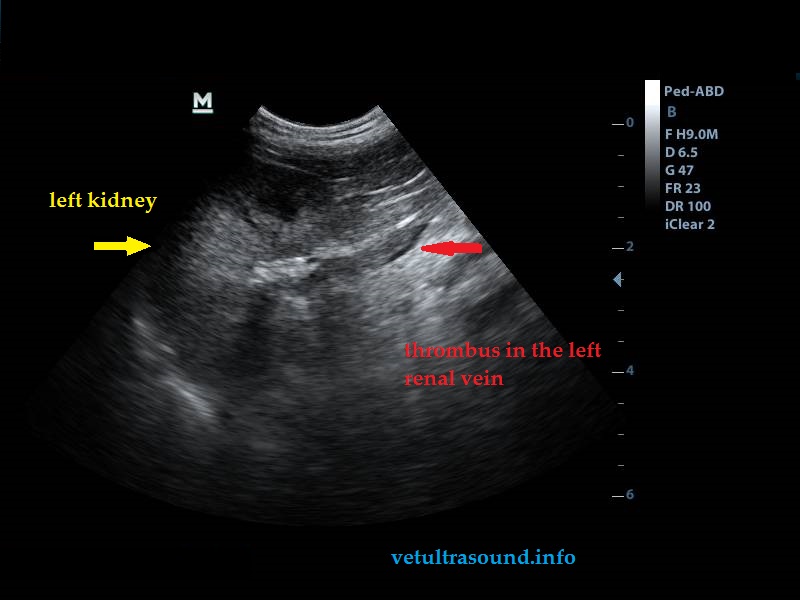

- Thromboses were present on the right and left renal vein due to stenosis of the caudal vena cava.

Infiltration of the caudal vena cava caused by the left adrenal gland mass, thromboses of the right and left renal veins, lesions potentially metastatic in the liver and clinical manifestation of pancreatitis probably induced by high levels of corticosteroids.